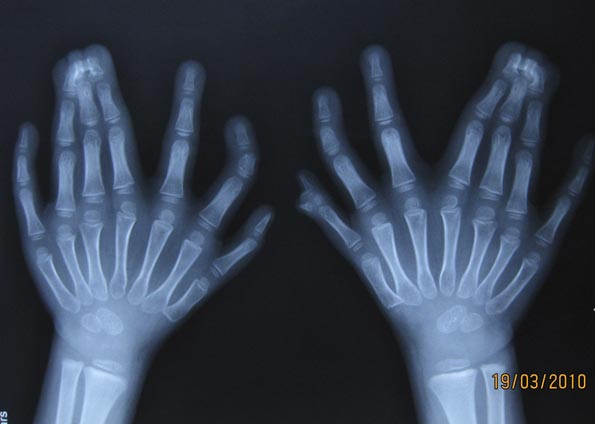

Radiografia feita no mesmo dia mostra as mãos da criança. Um dos dedos extras não é visível na imagem. (Foto: Reuters)